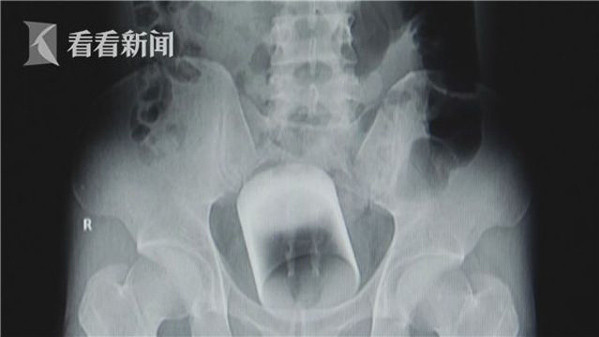

| Hình ảnh chiếc cốc khi được chụp X-quang. |